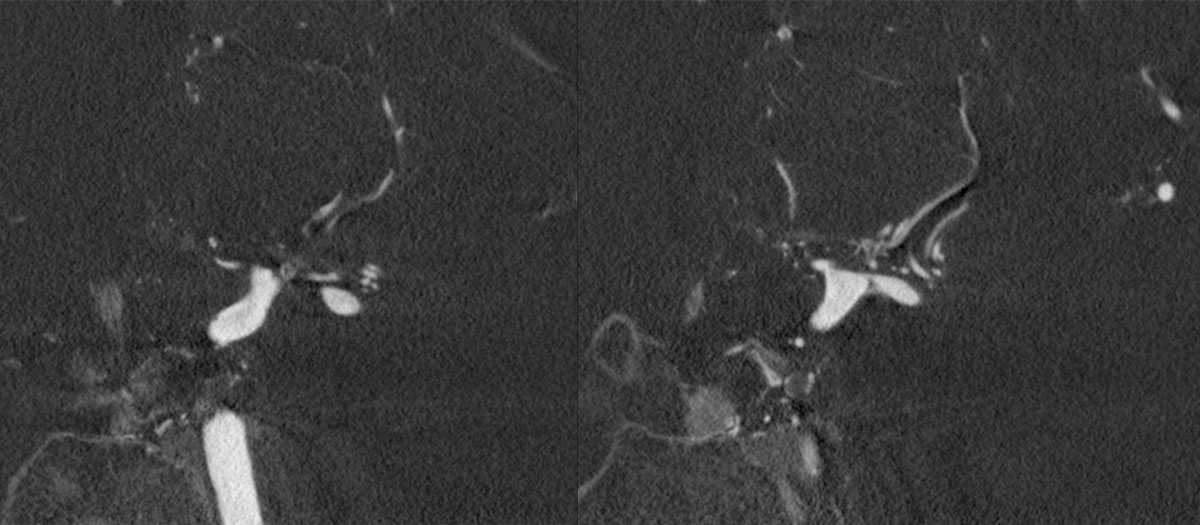

CT – CTA - CTP

DSA